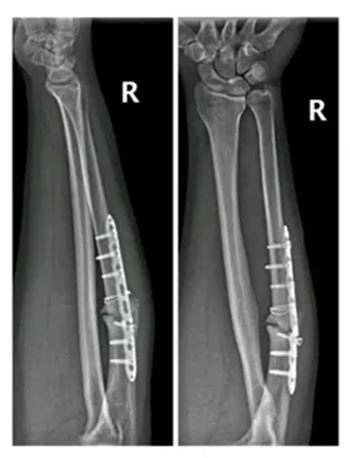

6年前因右侧尺骨骨折

在外院做了内固定手术治疗

到就近医院检查发现钢板断裂

后至郑州大学五附院骨科一病区就诊

骨科一病区主任徐明杰、主治医师张鹏飞通过问诊、查体并结合影像学检查资料,诊断为:尺骨骨不连

经过沟通,刘先生充分认识了自己的病情,并积极要求手术治疗。

徐明杰主任团队为他做了尺骨骨不连翻修+取髂骨植骨术,术后患者恢复良好。